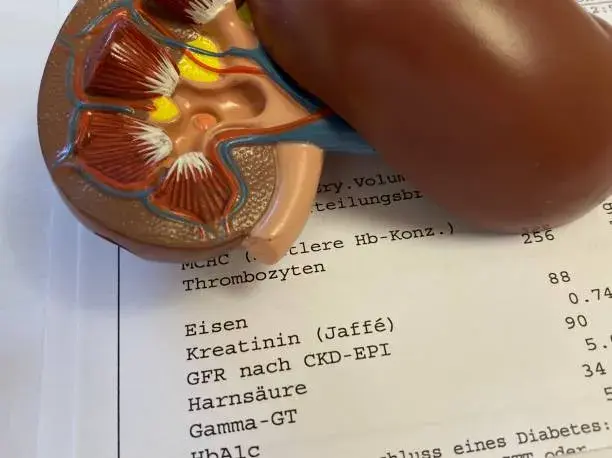

¿Cuál es el límite de consumo de proteínas sugerido por el KDIGO para la ERC en 2023?

¿Cuál es el límite de consumo de proteínas sugerido por el KDIGO para la ERC en 2023?